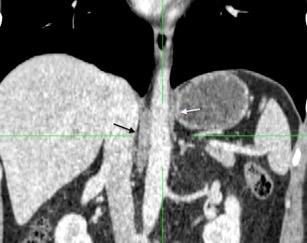

Nódulos pulmonares múltiples. (flechas verdes). Masas paratraqueales. (flechas amarillas). Dudoso ensanchamiento retrocrural (flechas negras). sigue….

Ttawfik A et al. Trans-diaphragmatic Pathologies: Anatomical Background and Spread of Disease on cross-sectional Imaging. Current Problems in Diagnostic Radiology. 2021.

T. mixto de células germinales del testículo

izquierdo Metástasis pulmonares. (flechas verdes). Ganglios paratraqueales. (flechas amarillas). Ganglios retroperitoneales (flechas negras)

Tawfik A et al. Trans-diaphragmatic Pathologies: Anatomical Background and Spread of Disease on cross-sectional Imaging. Current Problems in Diagnostic Radiology. 2021.